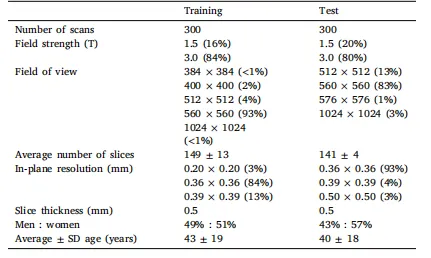

Table 1Acquisition details of the challenge dataset.

表1 挑战赛数据集的采集详情